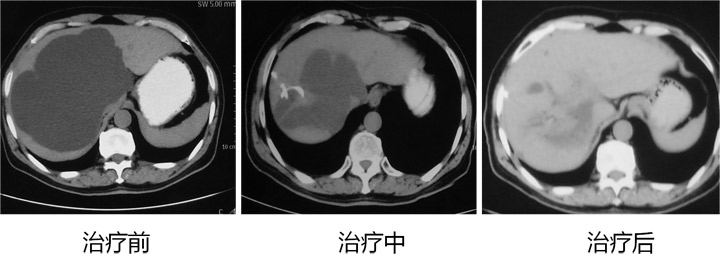

肝海绵状血管瘤为肝脏最常见的良性肿瘤,约占肝脏良性肿瘤的84%,好发于女性,发病率为男性的4.5-5倍。多见于30-60岁。肿瘤90%为单发,10%为多发。肿瘤直径从2mm到20cm...